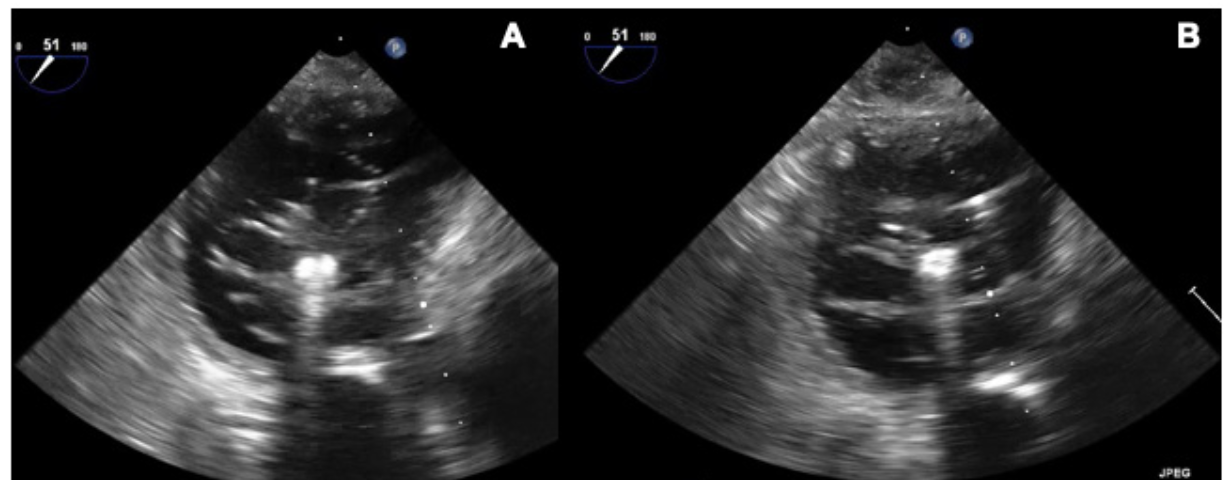

To the best of our knowledge, this is the first report of simultaneous grasping of the 3 leaflets during TriClip (Abbott Cardiovascular) implantation. The final valve configuration with a triple orifice (Figure 3) resembled the result of the clover surgical technique. This technique should be considered in selected cases of challenging grasping.